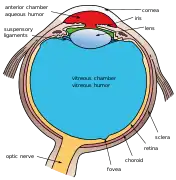

Additional images

The structures of the eye labeled Another view of the eye and the structures of the eye labeled